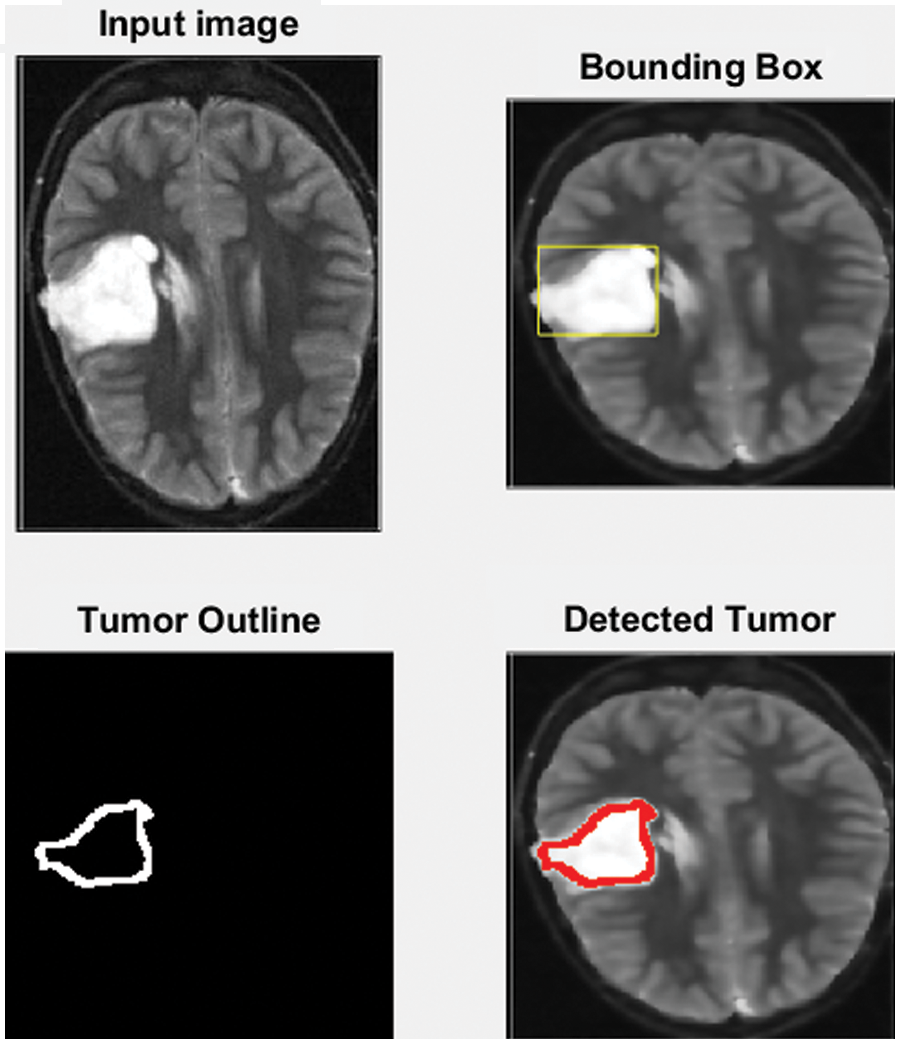

MATLAB is used in this research to conduct numerous experiments on a machine that runs Windows 11 Pro. The specifications are an Intel Chip of Core i7 of 8th generation, the clock speed is 2 GHz, and the RAM size is 16 GB. The dataset from the Kaggle website contains 3865 images of patients diagnosed with a brain tumor or no tumor. These MRIs were utilized to verify the precision, accuracy, recall, and correctness of the presented method in this research. Figs. 7–9 illustrate the obtained results for different MRIs. Each figure contains four subgraphs in which (A) is an input image in the upper lefthand corner, (B) is the detected potential area (tumor) bounded by the yellow rectangular box in the upper right corner, (C) is the detected tumor outline in the bottom left corner and (D) in the bottom right corner shows the detected tumor in red. The performance evaluation is detailed in two forms, which are quantitative and qualitative, of the obtained accuracy, precision, and recall. These three metrics are considered the most critical factors, and several studies use them to measure the developed algorithms. The presented system has evaluated the whole dataset. In the final phase, the proposed system receives inputs from both classifiers, as depicted in Fig. 4. The computed performance metrics are evaluated for the whole dataset, and the average value is taken for every metric. This section mainly focuses on evaluating the required factors and assessing them against implemented systems of the literature review. The dataset contains different sizes, which are resized to speed up the processing time. Figs. 7–9 provide a brief detection and classification results analysis when applying ten distinct runs. These three figures indicate that the proposed system has proficiently identified and classified the images under different runs. For instance, the system reached 92.3%, 93.51%, and 92.87% for accuracy, precision, and recall, respectively, in the first distinct run, and these figures increased as the number of distinct runs increased. The maximum obtained accuracy was 99.47% which is higher than measured. Fig. 10 illustrates the chart of the obtained values of the considered three performance metrics for ten distinct runs. One represents accuracy, two refers to precision, and three represents recall in the same figure. This graph shows that the accuracy increases after each distinct run while the precision and the rise in recall slightly reach an acceptable level of over 99%.

Figure 7: The input MRI and the detected tumor

Fig. 7 depicts the process of the implemented method. A yellow rectangle around it bounds the detected tumor, as shown in the upper right corner of the figure. The cancer is then outlined in the bottom left corner in red, as shown in the bottom right corner.

The developed algorithm also outlines tumors to justify and validate the correctness of the presented method. The detected tumor in Fig. 7 was slow-growth, while Figs. 8 and 9 show that the algorithm detected an aggressive or malignant tumor. In the previous three figures, Figs. 7–9, the proposed algorithm identified the tumors and classified them correctly.